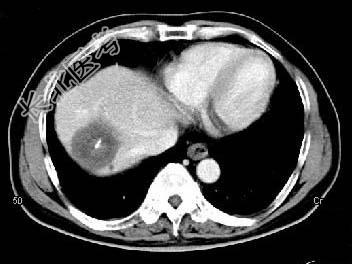

- 单项选择题根据所提供的图像,最可能的诊断是 ( )

A、肝内多发血管瘤

B、肝多发血管瘤并肝癌

C、多发肝囊肿

D、胆管细胞癌

E、以上都不是